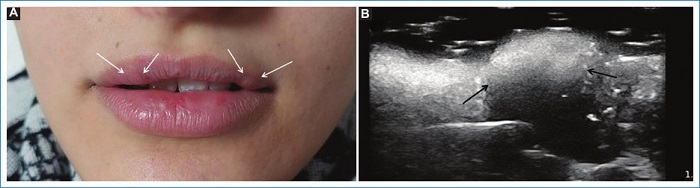

Del grupo 1 (n = 53, 63% del total de pacientes), 51 (96,2%) pacientes eran de sexo femenino y 2 (3,7%) de sexo masculino, 24 (45,2%) no presentaban rellenos previos, 15 (28,3%) presentaban ácido hialurónico (AH) y 14 (26,4%) tenían rellenos permanentes (biopolímeros, silicona y polimetilmetacrilato). Además, 12 (22,6%) pacientes de este grupo presentaron variantes anatómicas, de los cuales solo uno tenía un relleno previo de AH. Entre las variantes encontradas se mencionan arterias angulares, labiales, nasal dorsal y temporal profunda en sitios habituales de inyección de rellenos, glándulas parótidas prominentes y venas intercantales prominentes en sitios de inyección frecuentemente utilizados (Figs. 1, 2 y 3). En este grupo se presentaron 2 (3,7%) pacientes con prótesis faciales. Del total de pacientes que integraron este grupo, el informe ecográfico modificó la conducta del médico estético en el 60% (32) de ellos.

Con respecto a la topografía de las arterias labiales superior e inferior, se ha publicado que generalmente se encuentran en el plano submucoso (58,5%), seguido del plano intramuscular (36,2%) y menos frecuentemente subcutáneo (5,3%)9,10. En este sentido, un sitio habitualmente utilizado de inyección es el plano superficial subcutáneo para evitar un compromiso vascular.

En nuestro trabajo encontramos cinco pacientes con arterias subcutáneas (superficiales), hallazgo que condicionó un cambio en la conducta del médico inyector, si bien se mantuvo el plano superficial del relleno, se inyectó menor cantidad y más lento para reducir el riesgo de compromiso vascular.